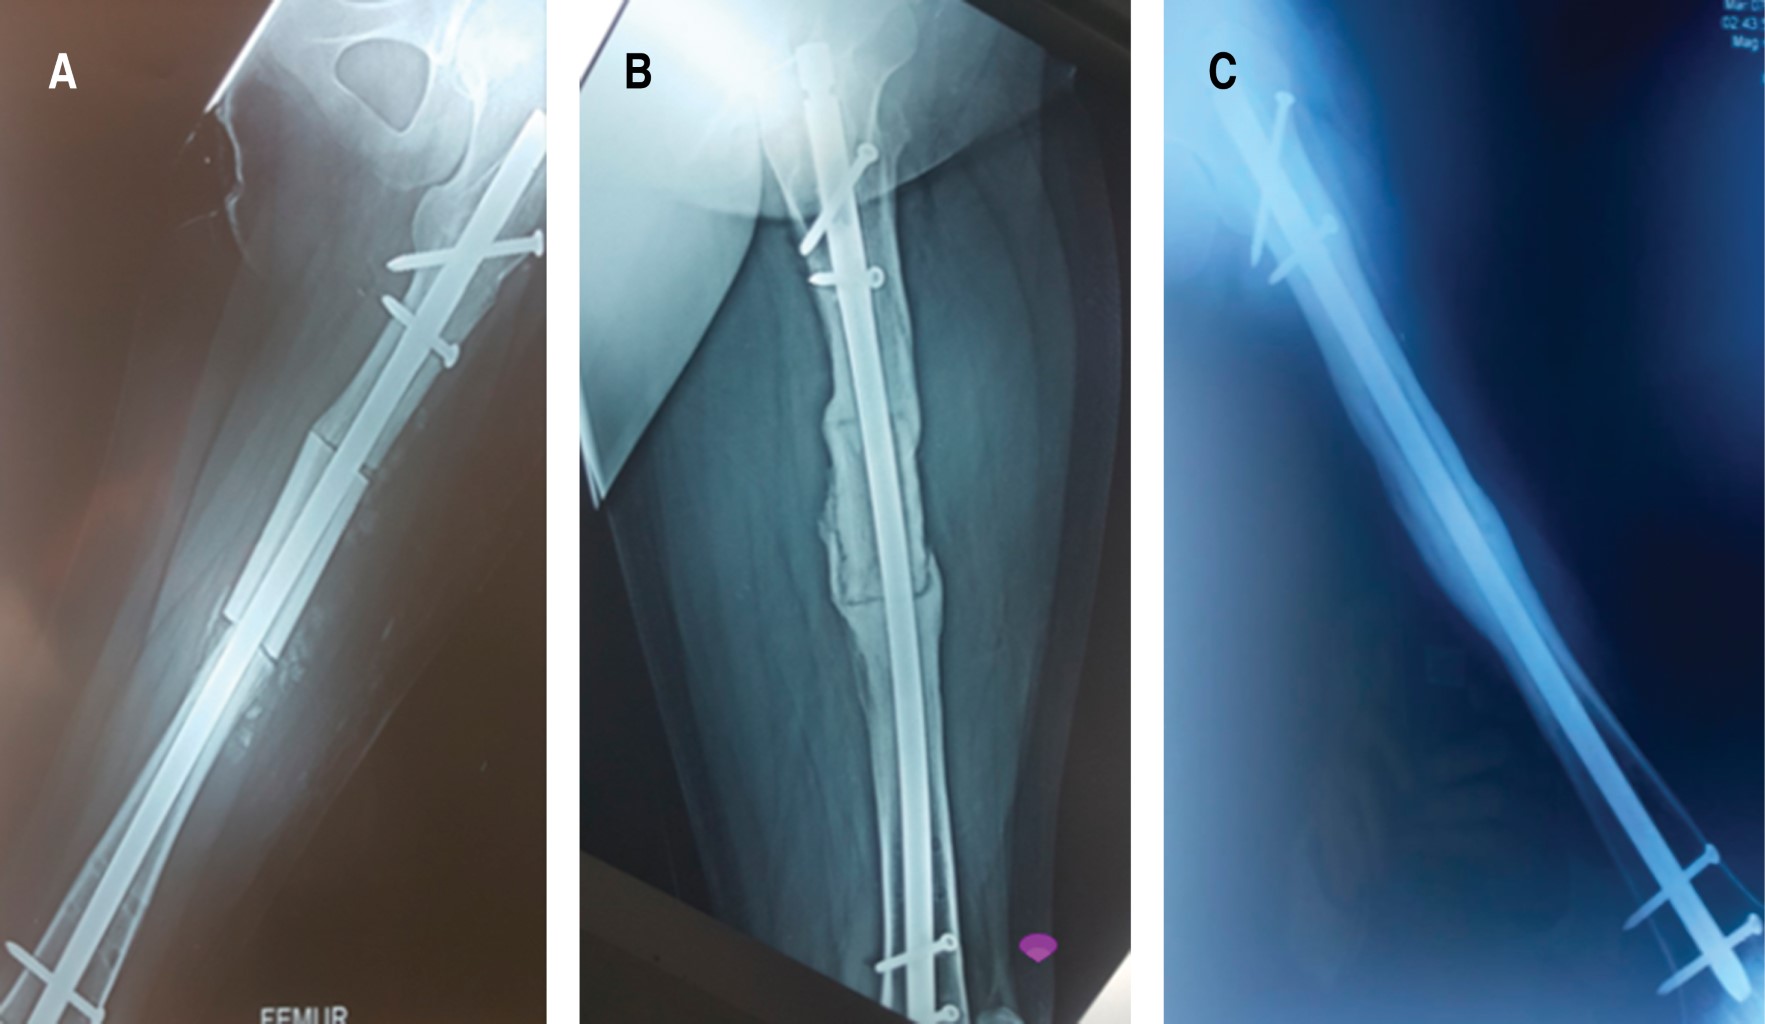

Pseudoarthrosis is a complication that poses a challenge for the orthopedist. If is associated with bone loss, a salvage surgery is indicated. There is no protocol for treatment for pseudoarthrosis with a "critical defect". The induced membrane technique, distraction osteogenesis, among others, has been described; however, the long time and elevated costs involved have opened a new landscape on the research of new protocols. The "diamond concept" which is not only based of improving biomechanics, but also introduces biological stimulation as a pillar of treatment, was recently introduced. We present the case of a 16-year-old female patient with a femoral shaft fracture after a traffic accident, treated initially with a centromedullar blocked nailing that progresses to pseudoarthrosis, presenting a 5 cm bone loss. Treatment consisted of removing the centromedullar blocked nail, resection of the nonviable bone segment, osteosynthesis with another centromedullar blocked nailing, placement a 7 cm diaphyseal allograft, platelet-rich plasma (PRP), matrix allograft, and bone chips, thus achieving radiographic and clinical consolidation; restoring limb function in a shorter time, considering the PRP as the main orthobiological element in this case.

Figure 3

Figure 4

Figure 5